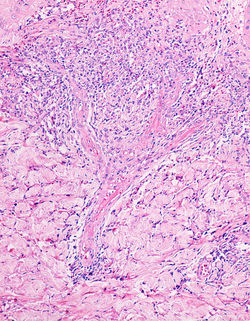

Se trata de una neoplasia vascular benigna infrecuente, descrita inicialmente por Hunt en 1991 (1). Esta lesión se presenta en adultos jóvenes, con un ligero predominio en el sexo femenino. Aunque su etiología sigue siendo desconocida, se han reportado asociaciones con inmunosupresión, embarazo y uso de anticonceptivos (2). Clínicamente se describe como una placa única asintomática eritematoviolácea, de bordes definidos y tamaño entre 0.5 a 2 cm, localizada en tronco y extremidades (F1) (3).

Microscópicamente, se observa proliferación no circunscrita de vasos sanguíneos de pared delgada, tapizados por endotelio sin atipias y ramificados. Estos vasos se distribuyen en la dermis reticular superficial y profunda (F2-F4) con un patrón infiltrativo entre las fibras de colágeno (F5) e invasión a los anexos cutáneos, siendo muy típica la infiltración al músculo piloerector (F6-F7) (2). Se han descrito casos excepcionales que presentan infiltrado linfoplasmocitario, endotelio con aspecto “en tachuela” y focal extravasación de eritrocitos (3,4). Mediante inmunohistoquímica se observa positividad para marcadores endoteliales como CD31 (F8), CD34, ERG y WT1 (F9); con negatividad para HHV8, D2-40 (F10) y GLUT1 (5).